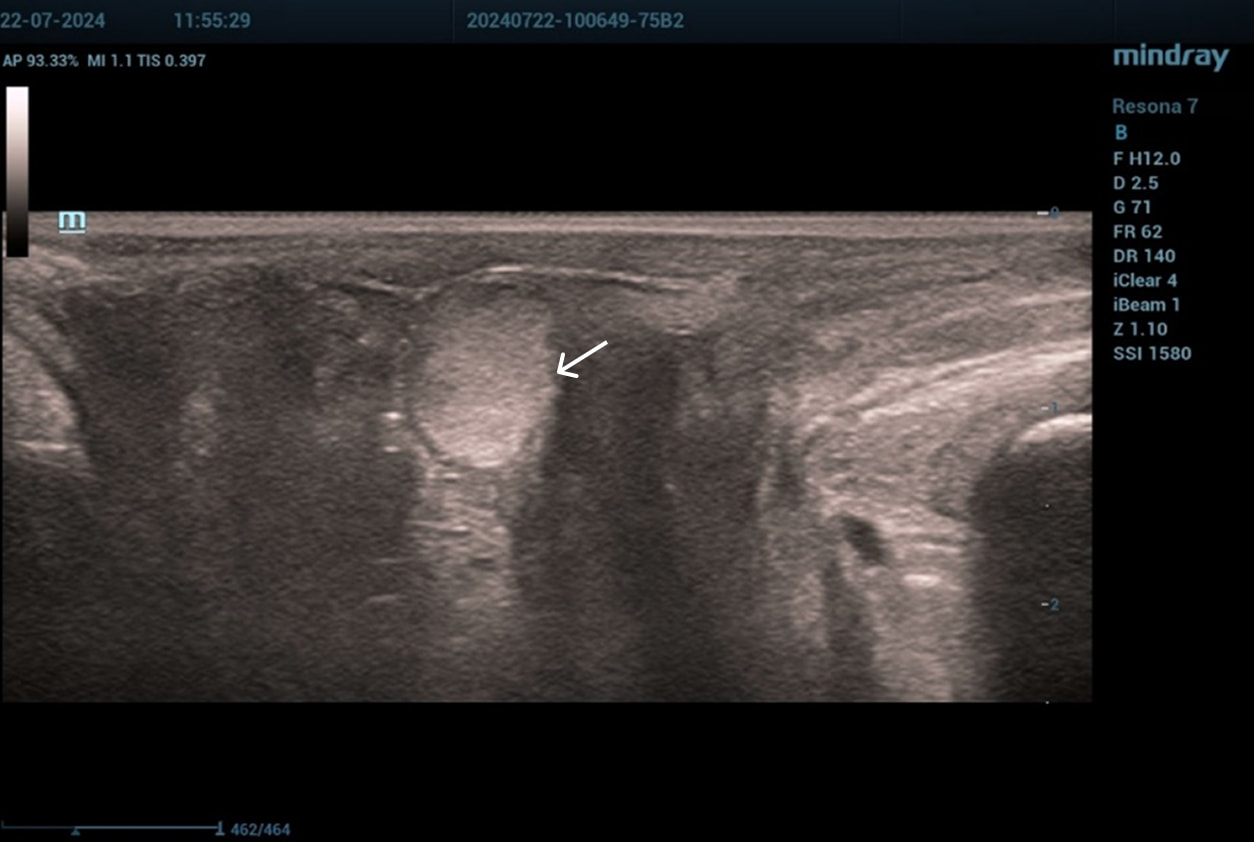

Осмотр: периуретрально визуализируется мягко-эластичное образование размерами 0,5×0,5 см.

Диагноз: хронический цистит (посткоитальный). Дистопия уретры. Опущение передней стенки влагалища I степени. Состояние после периуретрального введения геля на основе гиалуроновой кислоты.